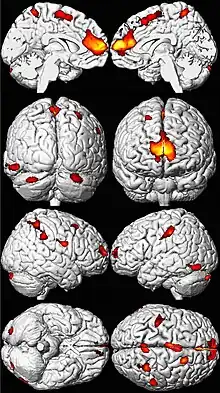

.png.webp)

Lead poisoning can cause a variety of symptoms and signs which vary depending on the individual and the duration of lead exposure.[27][28] Symptoms are nonspecific and may be subtle, and someone with elevated lead levels may have no symptoms.[29] Symptoms usually develop over weeks to months as lead builds up in the body during a chronic exposure, but acute symptoms from brief, intense exposures also occur.[30] Symptoms from exposure to organic lead, which is probably more toxic than inorganic lead due to its lipid solubility, occur rapidly.[31] Poisoning by organic lead compounds has symptoms predominantly in the central nervous system, such as insomnia, delirium, cognitive deficits, tremor, hallucinations, and convulsions.[26]

High blood lead levels in adults are also associated with decreases in cognitive performance and with psychiatric symptoms such as depression and anxiety.[81] It was found in a large group of current and former inorganic lead workers in Korea that blood lead levels in the range of 20–50 μg/dL were correlated with neuro-cognitive defects.[82] Increases in blood lead levels from about 50 to about 100 μg/dL in adults have been found to be associated with persistent, and possibly permanent, impairment of central nervous system function.[63]

Lead exposure in children is also correlated with neuropsychiatric disorders such as attention deficit hyperactivity disorder and anti-social behaviour.[76] Elevated lead levels in children are correlated with higher scores on aggression and delinquency measures.[5] A correlation has also been found between prenatal and early childhood lead exposure and violent crime in adulthood.[72] Countries with the highest air lead levels have also been found to have the highest murder rates, after adjusting for confounding factors.[5] A May 2000 study by economic consultant Rick Nevin theorizes that lead exposure explains 65% to 90% of the variation in violent crime rates in the US.[83][84] A 2007 paper by the same author claims to show a strong association between preschool blood lead and subsequent crime rate trends over several decades across nine countries.[85][86] Lead exposure in childhood appears to increase school suspensions and juvenile detention among boys.[87] It is believed that the US ban on lead paint in buildings in the late 1970s, as well as the phaseout of leaded gasoline in the 1970s and 1980s, partially helped contribute to the decline of violent crime in the United States since the early 1990s.[86]